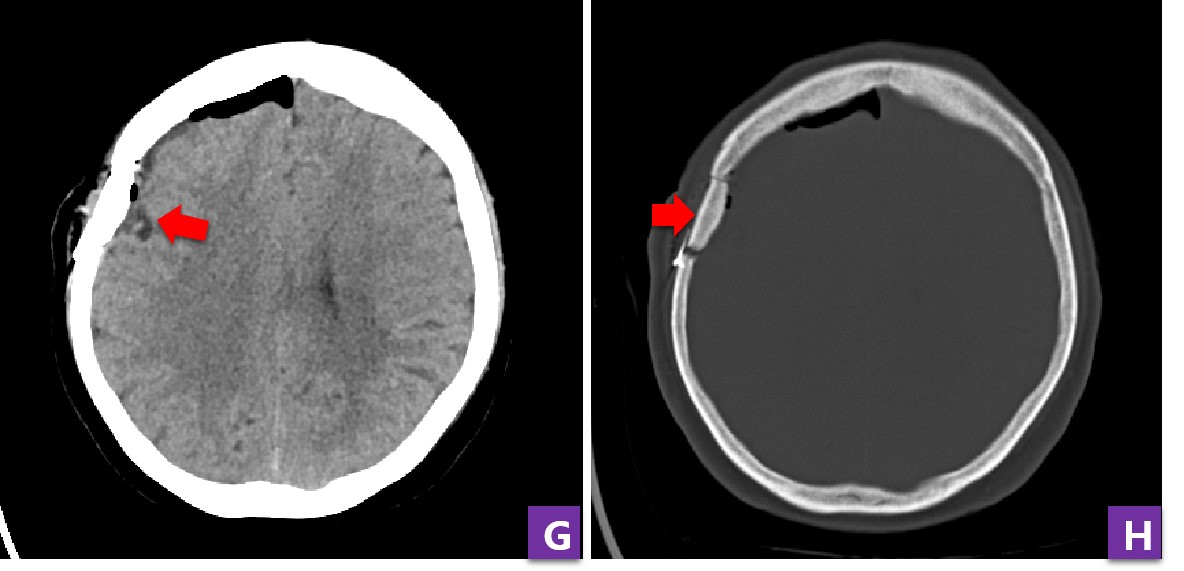

图2 患者术前CT及MRI发现右额部肿瘤

病人最早是因为头晕来医院检查,拍了头CT发现颅内竟然长了个2cm左右的瘤子,后来进一步做了头颅磁共振检查,最终考虑肿瘤是起源于脑膜的良性肿瘤——脑膜瘤。这个病人的脑膜瘤虽然小,但却临近大脑皮层功能区,如果放任不过,肿瘤还会持续生长,将来可造成头疼、偏瘫、癫痫等问题。

图3 患者增强MRI提示肿瘤均匀强化,起源于硬脑膜

病人目前肿瘤较小,早期开颅手术,不仅创伤小,而且容易根治肿瘤,但缺点是精准定位困难,有了神经导航的辅助,一切困难迎刃而解。在顺利完成肿瘤定位后,手术团队使用显微镜为病人进行肿瘤和病变硬膜的切除。